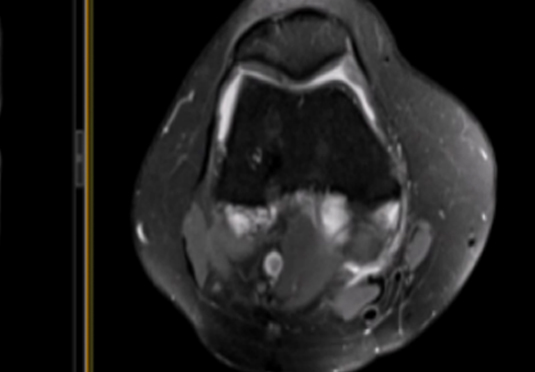

微創(chuàng)射頻消融術(shù)

適用于微創(chuàng)射頻熱消融術(shù)治療患者,引進(jìn)權(quán)威醫(yī)療團(tuán)體輔助引流。